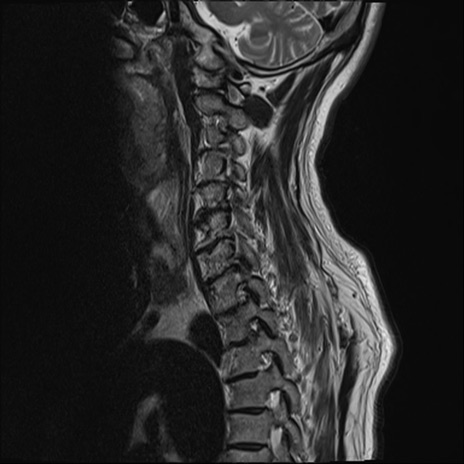

【整形】TIPS症例7 頚椎MRI T2WI(矢状断像)

頚椎MRI

T1WI(矢状断像)

矢状断像と横断像